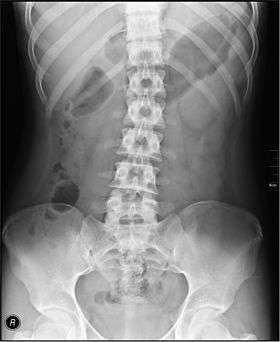

Diseases affecting the large intestine may cause blood to be passed with stool, may cause constipation, or may result in abdominal pain or a fever. Tests that specifically examine the function of the large intestine include barium swallows, abdominal x-rays, and colonoscopy.[3]:913–915